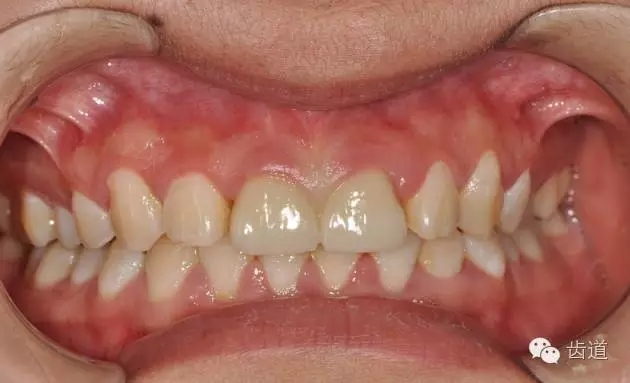

11、21全瓷氧化鋯修復(fù)

圖為永久粘固后即刻口內(nèi)照